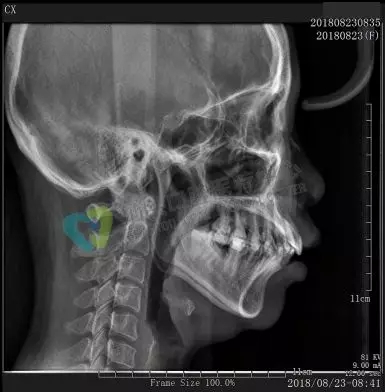

口腔全景牙片,是通过一次拍摄将全口牙齿和颌骨的影像清晰的显示在一张X光片上,可以清晰、完整的显示上颌骨、下颌骨全貌,上下颌牙列情况,牙槽骨情况,能够清晰显示上颌窦腔、窦壁、窦底情况以及颞颌关节情况,并对颌骨周围疾病的诊断提供准确有效的帮助。